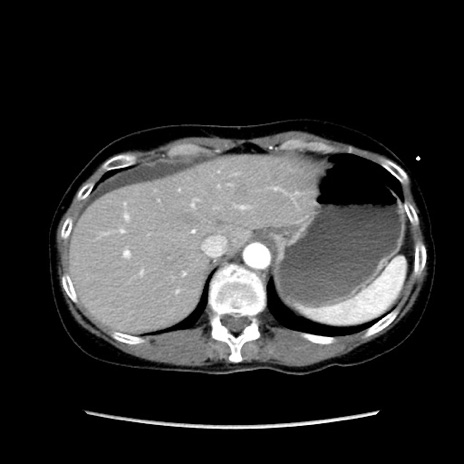

症例32(横断像)

【症例】40歳代 女性

【主訴】上腹部痛、嘔気・嘔吐

【現病歴】約9時間前頃から急に上腹部痛、嘔気、嘔吐が出現。改善しないため救急要請。

【既往歴】子宮頚癌(広汎子宮全摘術、放射線療法)、腸閉塞

【身体所見】腹部:平坦、軟、腸雑音亢進、上腹部を中心に腹部全体に圧痛あり。

【データ】WBC 8400、CRP 0.03